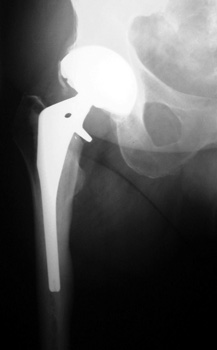

FRACTURE—periprosthetic, in traction

Fracture distal to femoral stem